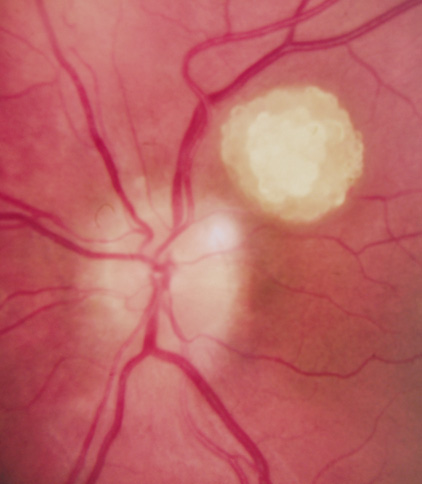

CNS hemangiomas are the most common tumor of VHL, affecting 60% to 80%, with a predilection for the cerebellum and spinal chord. An enlarging cystic component is a frequent finding in symptomatic tumors. Patients typically present in their early 30s; headaches or neck pain in affected individuals should not be ignored.172,173 On microscopy, CNS hemangiomas resemble retinal capillary hemangiomas. Their malignant potential is low.174 The treatment is surgical (Fig. 17, A and B).13

Fig. 17. Images from a 13-year-old boy with Von Hippel-Lindau syndrome. (a) Coronal postcontrast T1-weighted imaging reveals a cystic lesion with an enhancing nodule at the pial surface typical of a hemangioblastoma. (b) A second solid enhancing hemangioblastoma is seen at the craniocervial junction on a sagittal postcontrast T1-weighted image. (c) Associated cystic lesions (arrows) are seen within the pancreas.

PANCREAS.

Pancreatic lesions may be nonsecretory (most commonly cysts or cystadenomas) or secretory (islet cell tumor).179 In one study of 52 patients, 56% (29 patients) were found to have pancreatic lesions. The majority (19 of 29) had cystic changes only (Fig. 17C). Pancreatic lesions were the only abdominal manifestation of disease in 6 of 52 patients.180 In a separate study, pancreatic cysts did not show significant progression on follow-up examinations over an average period of 5 years.181 Like pancreatic cysts, islet cell tumors appear to be frequently asymptomatic.182